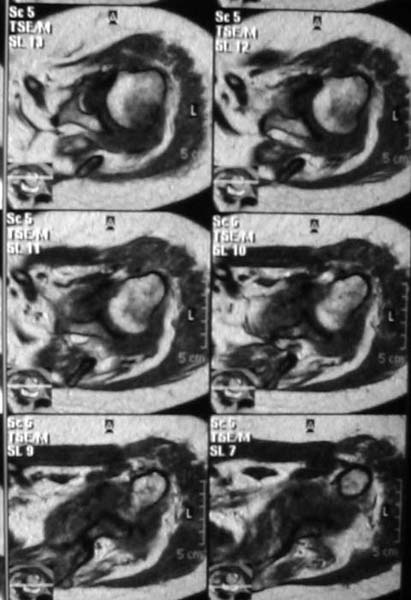

Уважаемые коллеги!Женщина, 60 лет. 3 недели назад упала с упором на отведенную левую руку. Почувствовала боль в левом плечевом суставе. За помощью не обращалась. 2 недели "мази и припарки". Затем - рентгенограмма (r1 и r2), жалобы на боли,ограничение движений...

Активное отведение 80 гр., при пальпации - головка плечевой кости безболезненно вправляется и тут же самостоятельно вывихивается. Наложена косыночная иммобилизация, рентгенография (r3) и МРТ.В нашем диагностическом центре МРТ исследование плечевого сустава выполнено впервые, опыта у нас маловато :(.Вопросы: уточнение диагноза? какие исследования провести? тактика лечения?

МРТ1МРТ2МРТ3МРТ4

Из того, что видно на недостаточно качественно отсканированных МРТ - нижний подвывих плеча и синовиит. Непонятный очаг по заднему контуру головки плеча (то ли артефакт, то ли косой срез, проходящий между головкой и большим бугорком). Сухожилия вращательной манжетки выглядят целыми. Неправильная форма нижней части labrum glenoidale - разрыв ?

И еще одно пожелание - МРТ костно-суставной системы ОБЯЗАТЕЛЬНО нужно проводить с использованием сканов с подавлением сигнала от жировой ткани (SPIR - на Филипсах, у Вас, как я вижу - Филипс; FATSAT - на других томографах, либо STIR - есть на любых аппаратах). Только так можно увидеть отек мягких тканей и костного мозга на фоне жировой ткани.

Плоскости при сканировании плеча обязательно должно быть 3

1. Ортогональная поперечная (аксиальная)

2. Косая корональная (параллельно длинной оси диафиза)

2. Косая сагиттальная (так же параллельно диафизу плеча)

1. На рентгене - нижний подвывих плеча и очаг остеолиза суставного бугорка с четкими контурами (вдавленный перелом на фоне остеопороза ? доброкачественная опухоль? аваскулярный некроз ? (хотя ни разу не слышал об аваскулярном некрозе плеча..)

2.выраженный выпот в полости сустава